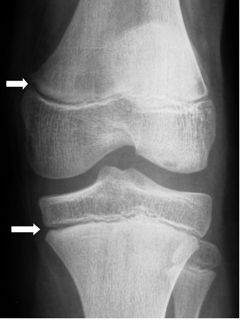

Les cartilages de croissance du genou vus de face en radiographie

L'âge de survenue de cette lésion est habituellement supérieur à 10 ans bien que quelques cas soient décrits chez des enfants plus jeunes (à partir de 6 ans). Le traumatisme est habituellement violent de sorte que cette lésion est volontiers rencontrée en traumatologie routière ou sportive. L'hémarthrose est généralement de grande abondance volontiers sous tension. Les radiographies standard du genou de face et de profil suffisent à mettre en évidence la fracture et à en apprécier le déplacement. Le volume réel du ou des fragments est du fait du caractère ostéochondral de la fracture toujours sous-estimé.